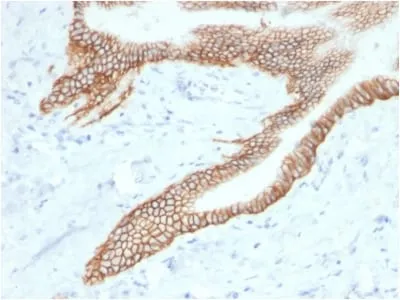

Anti-TACSTD2 / TROP2 (Epithelial Marker) (TACSTD2/2153), Biotin conjugate